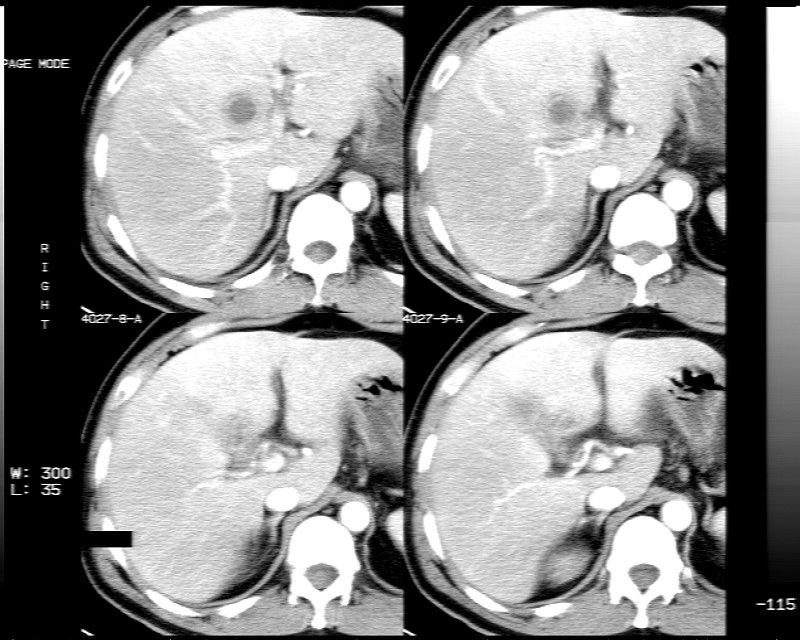

男性,52岁,腹痛,无发热,生化检查无明显异常,既往有胰腺炎病史,经治疗好转出院。

胆囊炎,肝脓肿(周围可见异常灌注)

1)考虑肝左叶内侧段肝脓肿,不排除转移瘤。2)脂肪肝。3)慢性胆囊炎。4)十二指肠降部肿瘤可能。

胆囊炎、脂肪肝、肝脓肿。